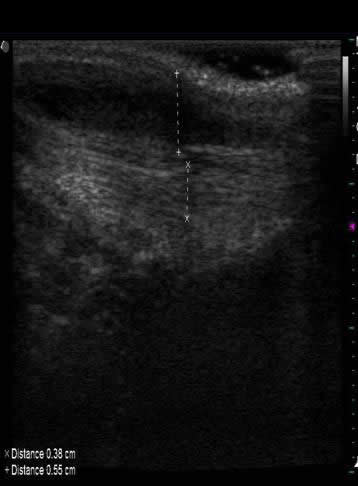

1) Ultrasonografía musculoesquelética inicial: Fotos 1 A y B. Imágenes corte longitudinal de bolsa sinovial.

(A) Se observa bursa distendida con contenido hipoecogénico (presencia de líquido). (B) Se observa con mayor detalle refuerzo acústico posterior delimitado por dos bandas hiperecoicas. En condiciones normales no suele apreciarse la bolsa sinovial.